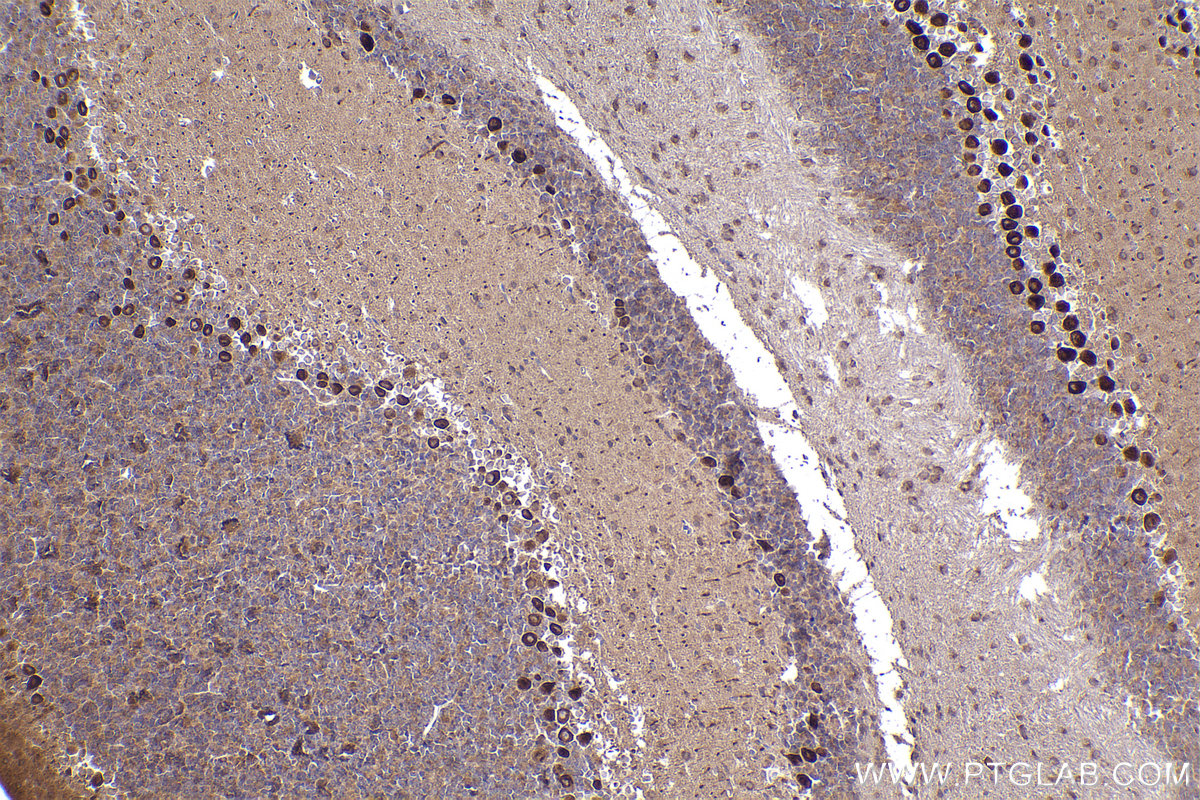

| Positive IHC detected in | mouse cerebellum tissue, human rectal cancer tissue Note: suggested antigen retrieval with TE buffer pH 9.0; (*) Alternatively, antigen retrieval may be performed with citrate buffer pH 6.0 |

| Immunohistochemistry (IHC) | IHC : 1:250-1:1000 |